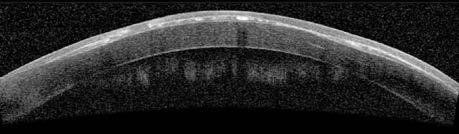

Se le realizó una tomografía de coherencia óptica de segmento anterior (OCT SA), donde se visualizan pequeñas áreas de hiperreflectividad compatible con los nidos epiteliales, además, se puede evidenciar zonas de adelgazamiento del flap corneal desde la periferia hacia el centro. A su vez, se observa el sector de amputación del flap por donde se produjo el

Imagen 1. Fotografía de la BMC donde se observa el crecimiento intraepitelial. A, obtenida con corte de luz blanca. B, tomada con luz azul observándose la tinción por pooling por irregularidad en el flap. Imagen 2. OCT SA OI donde se aprecian los nidos epiteliales hiperreflectivos.

crecimiento intraepitelial. (Imagen 2). La topografía presenta irregularidad en los anillos de plácido en OI concordante con la irregularidad epitelial. Se informa alterado el resultado del índice de dispersión objetiva (“Objective Scatter Index” u OSI) en el HD Analyzer, es un parámetro que brinda información respecto a la dispersión de la luz y a la calidad visual dependiendo de la opacificación de medios y la calidad de la lágrima.

Se llevó a cabo una conducta expectante administrando plasma rico en plaquetas. Luego de 6 meses del traumatismo presentó disminución de su visión en OI con AVMC de 20/50. Con el objetivo de evitar el melting corneal, retirar el crecimiento intraepitelial y mejorar la AV de la paciente, se decidió resolver quirúrgicamente el caso, realizando una flapectomía con desbridamiento y utilizando mitomicina C (MMC) como coadyuvante. Durante el procedimiento, al levantar el flap, se detectó un buttonhole central, motivo por el cual se decidió retirarlo. Luego se realizó pulido del lecho estromal con fresa, seguido por la colocación de MMC y, por último, se colocó una lente de contacto terapéutica (Imagen 3).

La evolución postoperatoria fue favorable con una AVMC de 20/20 en OI, sin evidencia de crecimiento intraepitelial remanente a la BMC (Imagen 4). La paciente refirió mejoría en su calidad visual, reflejada en el HD Analyzer postoperatorio. La OCT SA se evidencia epitelio sano. Actualmente, se encuentra en seguimiento luego de dos años del procedimiento con buena evolución.